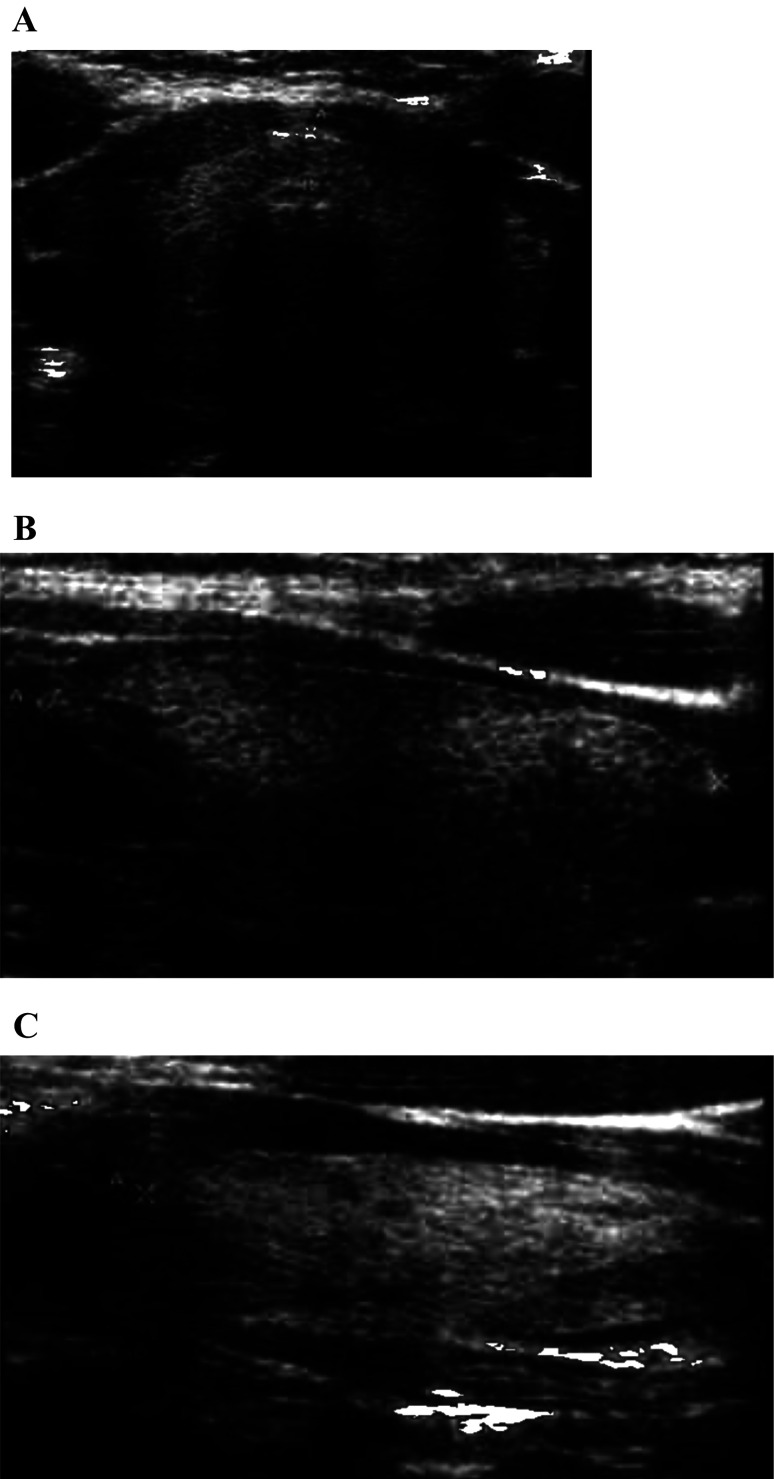

SLC26A4 可导致彭德综合征(Pendred Syndrome,PS)和非综合征性听力损失。PS是根据高氯酸盐排出试验异常、甲状腺肿和部分患者甲状腺功能减退来区分的。PS的甲状腺功能障碍的病理生理学与自身免疫性甲状腺疾病不同,它被认为是由碘的组织化缺陷引起的。一般认为,这两种疾病可能偶然同时存在,而SLC26A4可能在自身免疫性甲状腺疾病的病因中扮演重要角色。在此,我们描述了一例患有听力损失的女孩,她有两个致病的SLC26A4变体,并且甲状腺过氧化物酶(TPO)抗体检测呈阳性。她在 4 岁时被诊断出患有听力损失和前庭导水管扩大。耳聋基因筛查发现了两个致病性 SLC26A4 变体。由于 SLC26A4 变异可导致 PS,患者接受了全面的甲状腺检查。她的甲状腺属于轻度肿大的生理范围。虽然甲状腺功能检测结果正常,但患者的 TPO 抗体检测呈阳性。患者被诊断为 "疑似 PS "和 "疑似桥本氏甲状腺炎",这两种疾病都会增加甲减的发病风险。评估桥本氏甲状腺炎与 SLC26A4 变异体的并发症至关重要。

SLC26A4 causes Pendred syndrome (PS) and nonsyndromic hearing loss. PS is distinguished based on perchlorate discharge test abnormality, goiter, and hypothyroidism in some patients. The pathophysiology of thyroid dysfunction in PS differs from that of autoimmune thyroid disease, in that it is considered to be caused by an iodide organification defect. It is believed that both diseases may incidentally coexist, and that SLC26A4 may play an important role in the etiology of autoimmune thyroid disease. Herein, we describe a case of a girl with hearing loss who had two pathogenic SLC26A4 variants and tested positive for thyroid peroxidase (TPO) antibody. She was diagnosed with hearing loss and vestibular aqueduct enlargement at the age of 4 yr. Deafness gene screening revealed two pathogenic SLC26A4 variants. As SLC26A4 variants can cause PS, the patient underwent thorough thyroid examination. Her thyroid gland was within the physiological range of mild enlargement. Although thyroid function test results were normal, the patient tested positive for TPO antibody. The patient was diagnosed with "suspected PS" and "suspected Hashimoto's thyroiditis," both of which increase the risk of developing hypothyroidism. Evaluating the comorbidity of Hashimoto's thyroiditis with the SLC26A4 variant in terms of complications is critical.